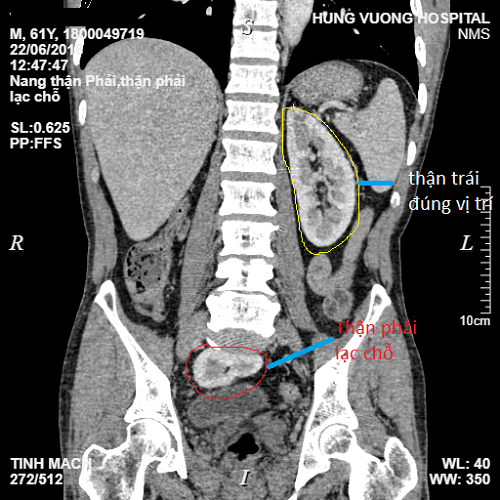

Bệnh nhân vào viện với các biểu hiện đau bụng âm ỉ vùng hố chậu phải lan ra sau lưng và vùng cột sống. Theo người nhà, bệnh nhân đau bụng âm ỉ kéo dài nhiều tháng nay. Gần đây, tình trạng đau bụng ngày càng tăng nên vào viện khám. Kết quả chụp CT cho thấy có hình ảnh nang nhỏ thận phải, đặc biệt thận phải lạc chỗ trong tiểu khung. Bác sĩ chẩn đoán bệnh nhân bị nang thận phải, thận phải lạc chỗ và cần phẫu thuật cố định thận phải.

CT cho thấy vị trí quả thận đi lạc. Ảnh: Vnexpress |